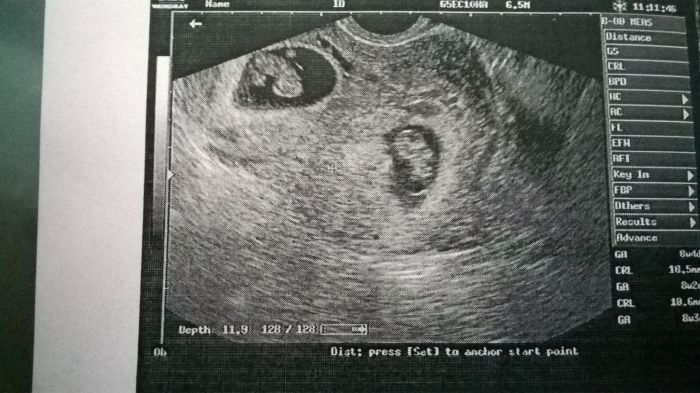

před 14 dny jsem tu psala, že krvácím a mám syndrom mizejícího dvojčete a dneska jsem byla na kontrole a mizející dvojče nezmizelo

čekám dvojčátka

obě dvě odpovídají stáří, mají krásná silná srdíčka a mají se čile k světu